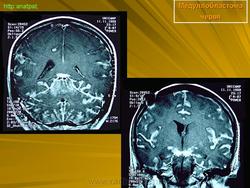

Медуллобластома - это опухоль, которая возникает из примитивных и эмбриональных клеток ЦНС. Локализируется исключительно в мозжечке и представляет 15-20% от детских опухолей мозга. 20% медуллобластом появляется в зрелом возрасте.

Это быстро растущая опухоль, очень злокачественна, имеющая тенденцию распространяться вдоль путей движения ликвора.

Вследствие локализации в мозжечке, обструкция путей циркуляции ликвора является достаточно частой и ранней, с последующей гидроцефалией. Синдром повышенного внутричерепного давления наряду с расстройствами равновесия, являются наиболее частыми и ранними признаками и симптомами.